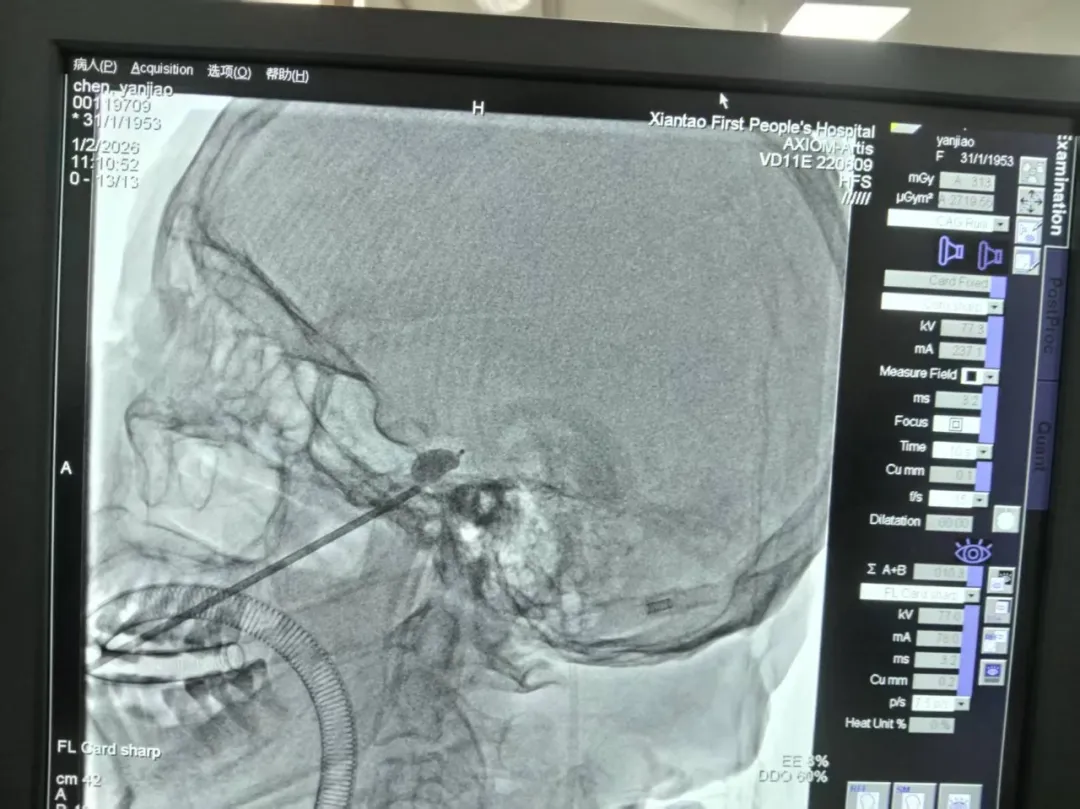

手术当日,曹方军主任带领孙道法副主任医师、王文举主治医师组成手术团队,在全麻下为刘奶奶实施手术。术中精准定位穿刺点,球囊顺利植入,精准压迫3.5分钟后泄压撤出。整台手术仅用时26分钟,患者生命体征平稳,意识清楚。